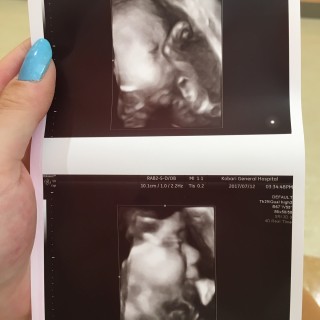

4D映像がすごい!こんなにはっきり映るのがびっくりしました。2人目ですけど、やっぱり感動しました!1540g元気な女の子です!もうすぐ会えるよ~